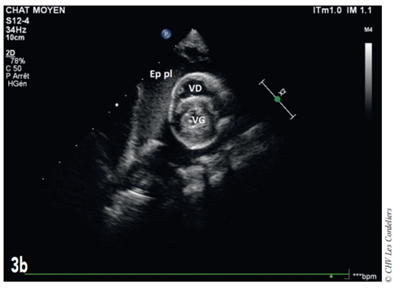

Fig. 3b – Échocardiographie du 23/09/2017 (J+42 jours) : mise en évidence d’un épanchement pleural (Ep pl) ; VG (ventricule gauche) ; VD (ventricule droit).

J+42 jours : malgré le bon état général, la dyspnée persiste. L’échocardiographie (Fig. 3a et 3b) montre une masse pulmonaire maintenant cavitaire s’étendant jusque dans le médiastin crânial et associé à un épanchement pleural.